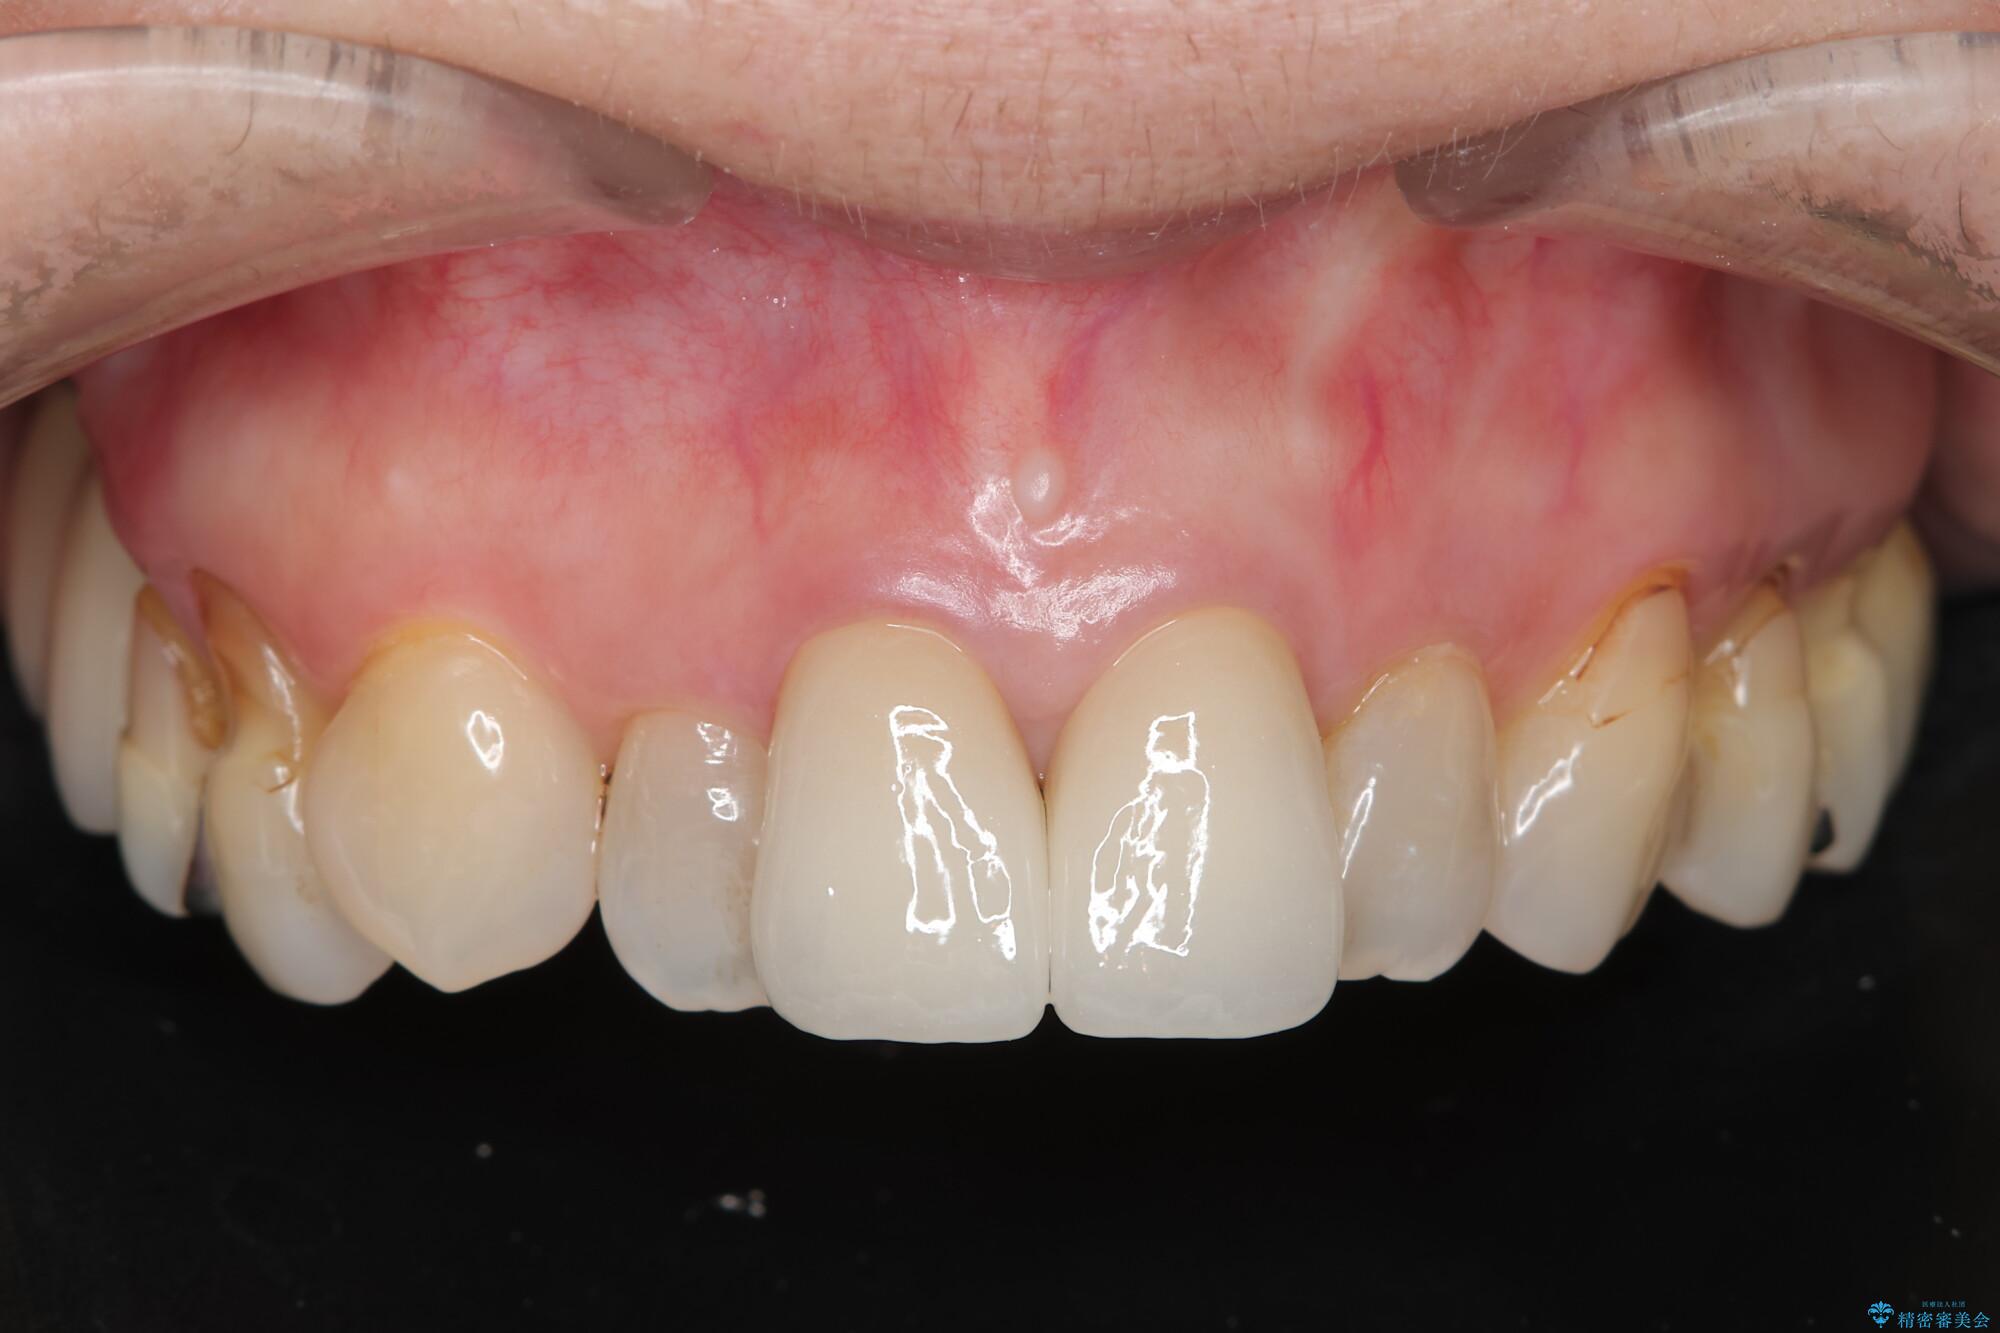

根管治療は行わず、クラウンのやり替えのみ行います。

審美性に優れるジルコニアクラウンによる治療を計画します。

黒ずみもなくなり、自然な色味で大変ご満足いただけました。